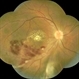

- CMV

- Condition/keywords

- vasculitis

- 70-year-old white female, III CMV, 20/40: OK; 5/200: infilesatire, vasculitis viluitis.